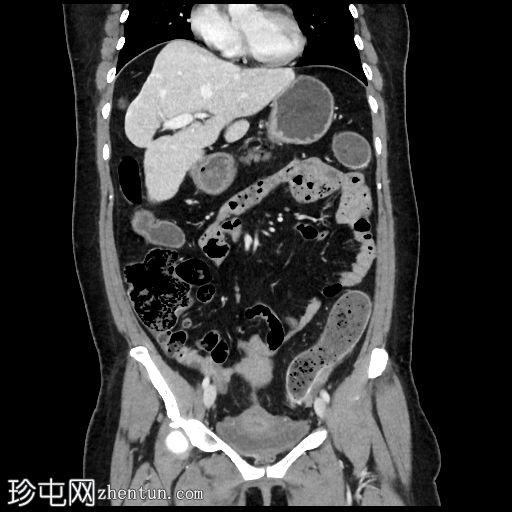

冠状位增强扫描(门静脉期)

线状包膜和实质钙化,呈“龟背样”外观

降结肠壁增厚(壁厚达7毫米),15厘米

段,直血管明显,伴脂肪浸润

乙状结肠和降结肠壁钙化